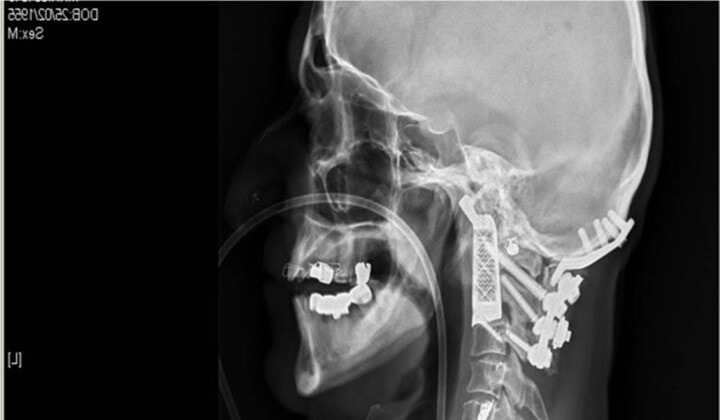

“凡爾納”奇跡:3D打印植入椎骨

來自澳大利亞悉尼威爾斯親王醫(yī)院的醫(yī)生莫布斯,利用3D打印技術(shù)做出了兩塊椎骨的替代品。完成了號稱“世界第一”外科手術(shù):醫(yī)生植入3D打印椎體。